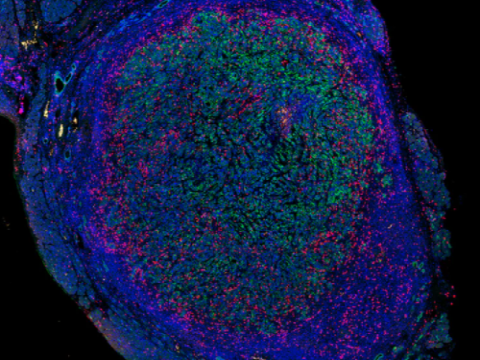

Thử nghiệm mới cho bệnh ung thư não truy tìm đột biến DNA trong máu và nước tiểu